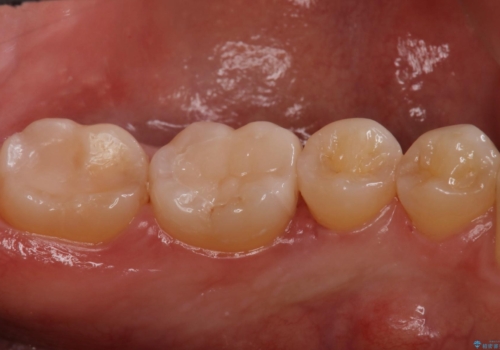

海外に引っ越す予定があり、見ため(審美性)強度ともに良い被せ物を希望されたため、セラミックインレーにて治療を行いました。

一部歯に保険治療で使用されている材料が劣化していたため、う蝕と一緒に取り除いて劣化の少ないセラミックに置き換わりました。